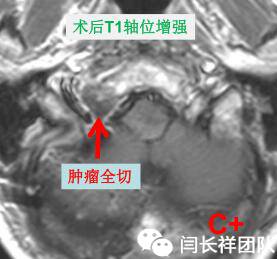

• 术前诊断:右侧舌下神经管占位

• 手术入路:右远外侧入路